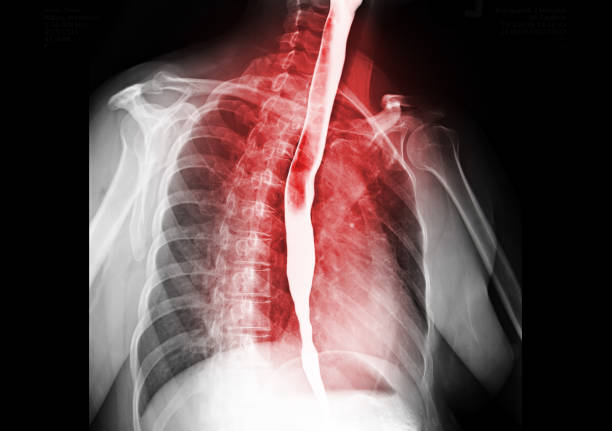

호흡곤란

호흡곤란은 식도암이 상당히 진행되었을 때 나타나는 증상입니다. 식도암이 진행되면 식도에 압력이 가해져 호흡곤란이 나타날 수 있습니다. 호흡곤란이 나타날 경우에는 식도암이 아닌 다른 호흡기 질환의 가능성도 있으므로, 식도암을 의심할 경우에는 반드시 전문의의 진료를 받아야 합니다.